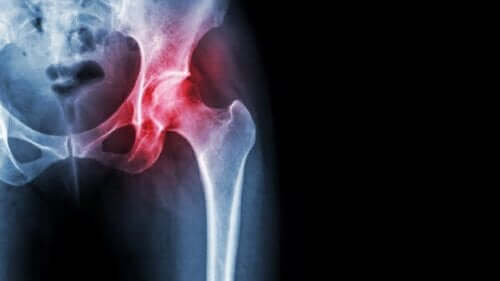

Avasculaire necrose van de heup

Avasculaire necrose wordt, zoals alle necrose, veroorzaakt door een gebrek aan bloedtoevoer naar de weefsels. In dit specifieke geval tast het de botten aan, wat tot vrij ernstige gevolgen leidt.

In dit artikel beschrijven we wat avasculaire necrose van de heupkop is, hoe dit de kwaliteit van leven van patiënten en hun behandelingsopties beïnvloedt.